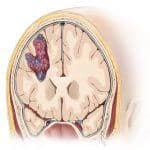

Chảy Máu Nhu Mô Não | Bài giảng CĐHA *

Chảy máu nhu mô não (intracerebral hemorrhage) là hiện tượng máu thoát ra khỏi thành mạch ở trong nhu mô não, chảy máu do chấn thương không nằm trong bệnh lý này. Chảy máu trong nhu mô não hay tụ máu trong nhu mô não có thể phối hợp cả chảy máu màng não gọi là chảy máu não-màng não…